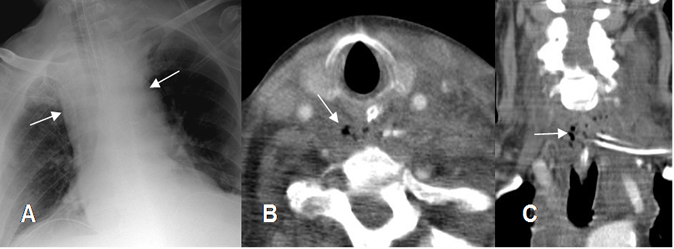

Fig 37. Mediastinitis.

A: Rx AP. Aunque la proyección magnifica el mediastino, este se aprecia ensanchado.

B: TAC axial y C: TAC reconstrucción coronal. Engrosamiento mediastinal, el cual contiene líquido. Se encuentran burbujas de aire a nivel retrotraqueal, por la formación de absceso.